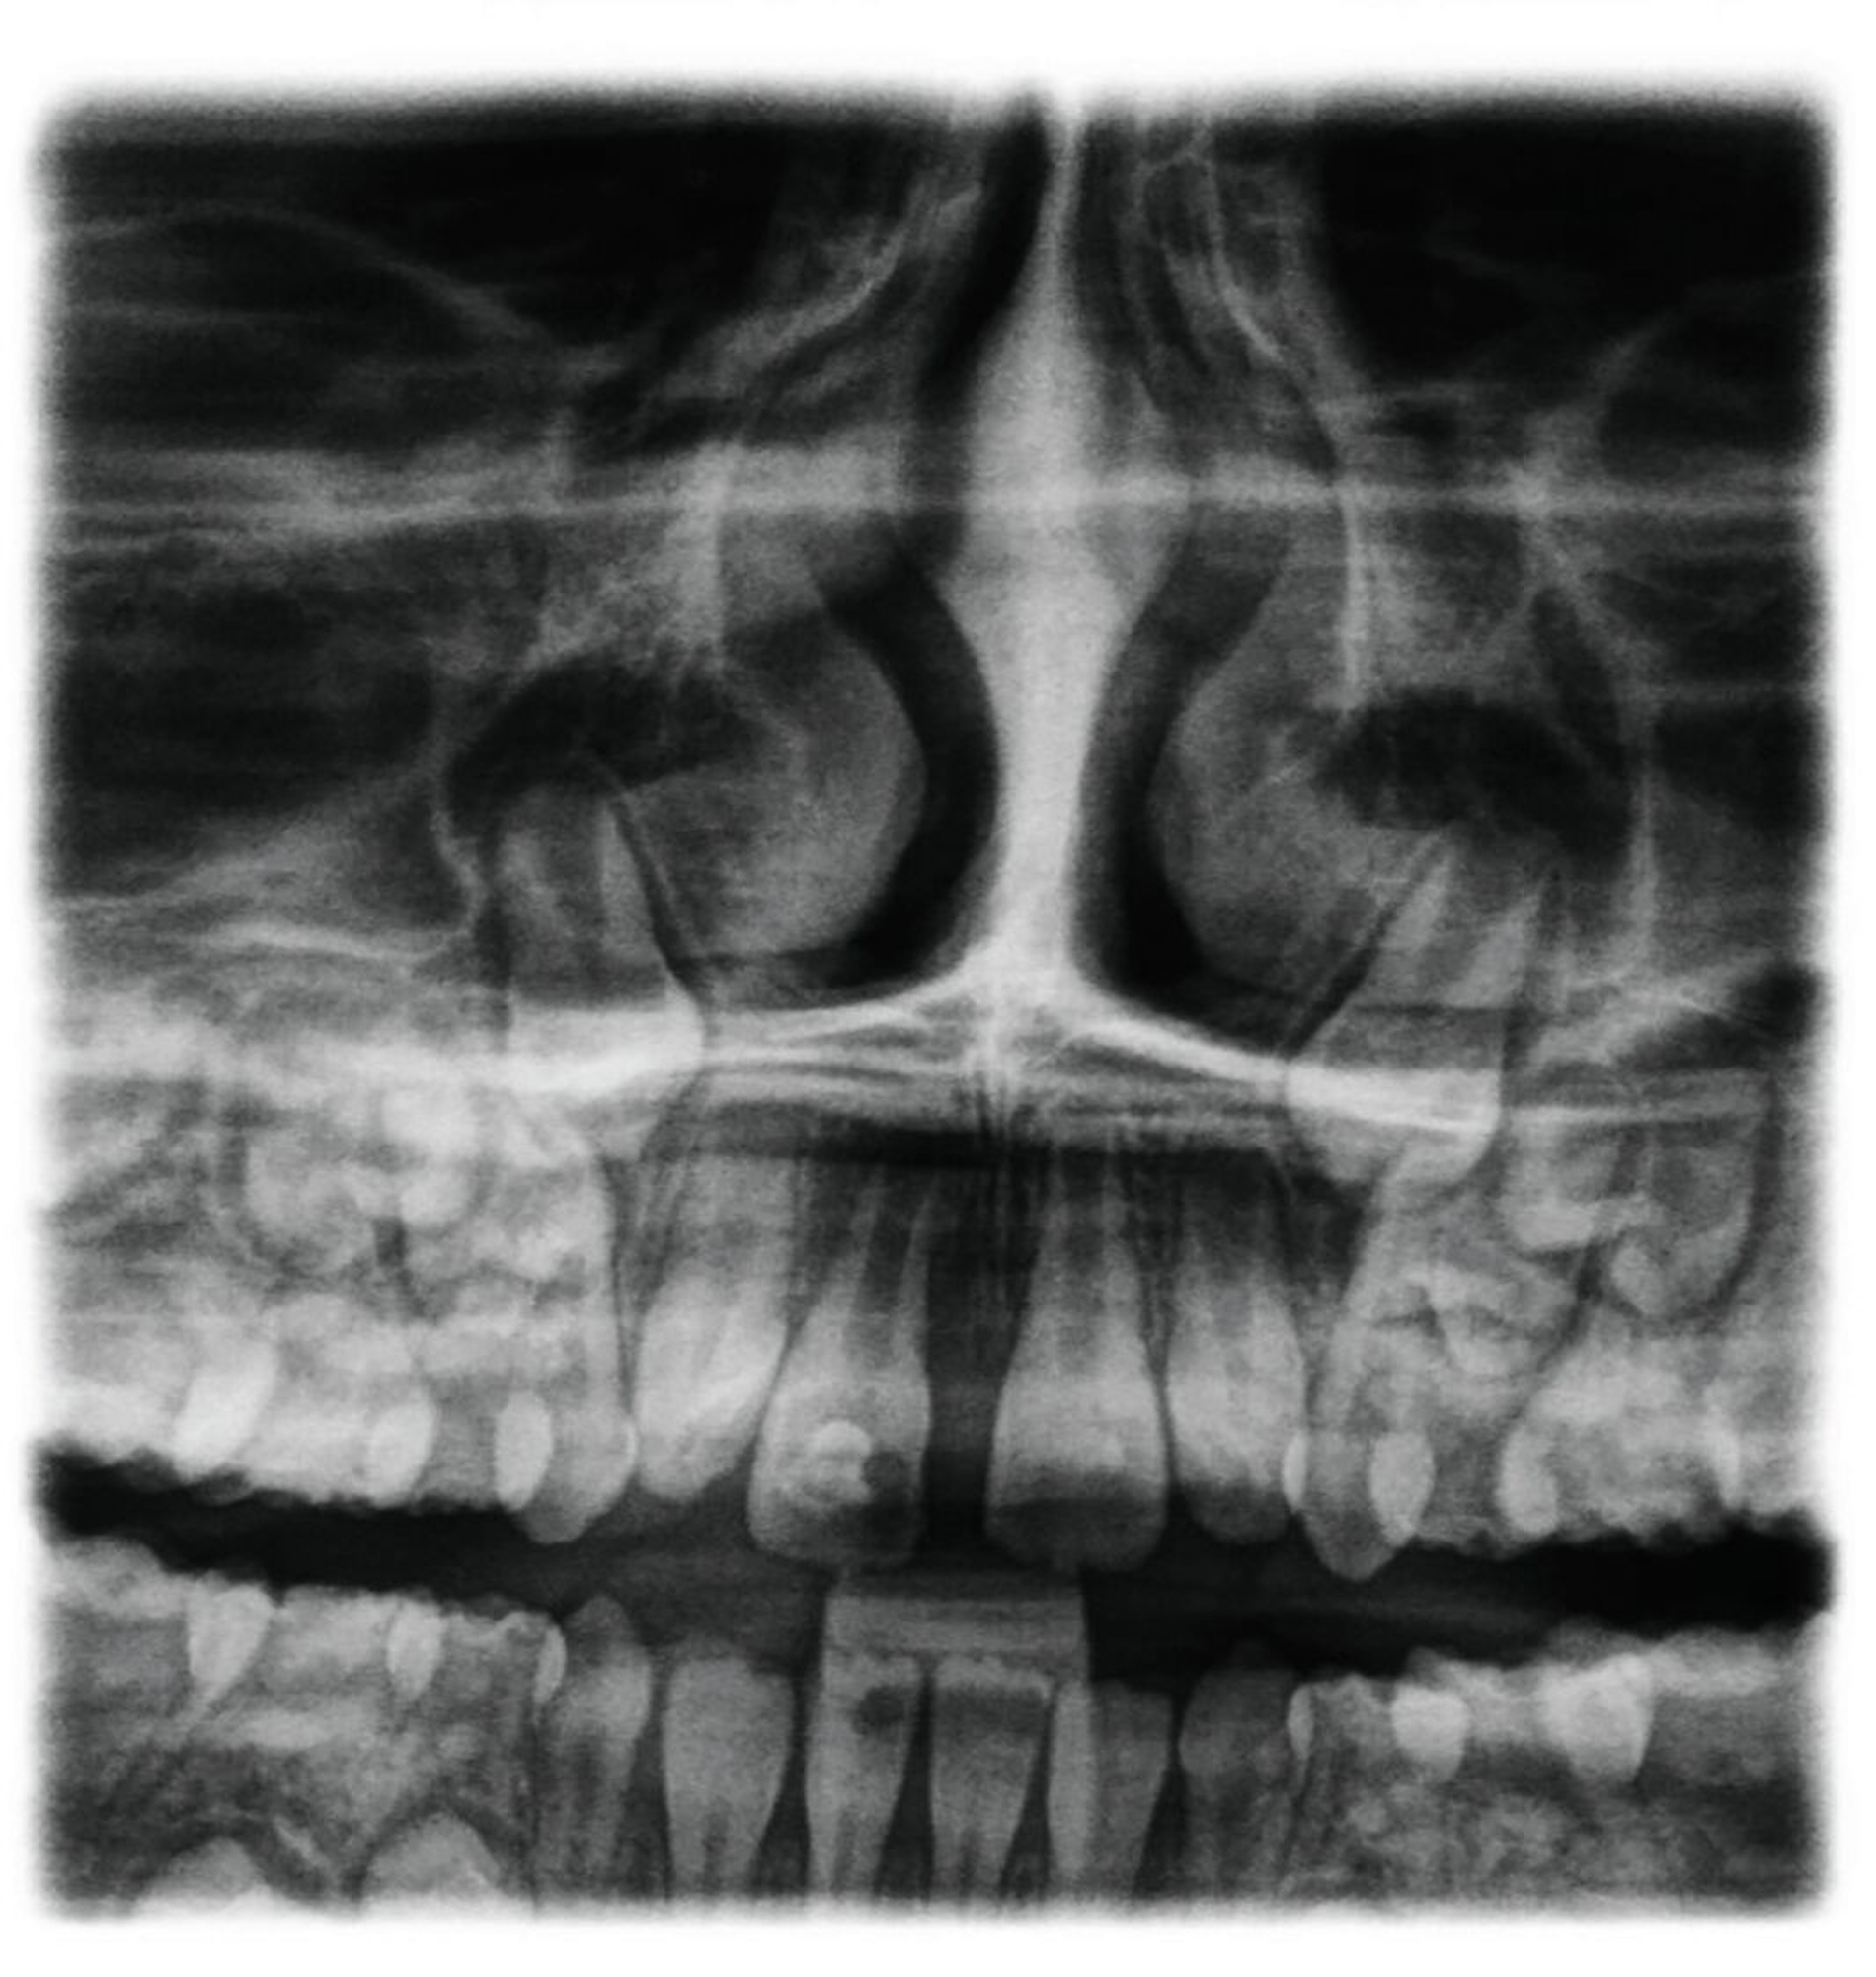

Ein neunjähriges Mädchen hatte bei einem Schlittenunfall den rechten oberen mittleren Schneidezahn verloren. Der Zahn 11 war nach einer extraoralen Lagerungszeit von mehr als 24 Stunden alio loco replantiert und mit einem Titan-Trauma-Splint von Zahn 12 bis 22 geschient worden. Drei Monate nach dem Unfall stellte sich die Patientin mit folgendem Befund vor (Abbildung 2):

Im OPG findet sich nach Replantation mit Pulpotomie (Abbildung 2a) bereits ein vertikaler Einbruch des krestalen Knochens, drei Monate später ist eine infektionsbedingte Resorption des Zahnes 11 erkennbar (Abbildung 2b). Alle vier Milcheckzähne zeigen im Alter von neun Jahren bereits deutlich reduzierte Wurzellängen aufgrund der natürlichen Exfoliation durch die im Durchbruch befindlichen bleibenden Eckzähne. Die Entscheidung fiel auf den Zahn 83 als Autotransplantat, da dieser zu diesem Zeitpunkt die längste Wurzel aufwies (Abbildung 2b).